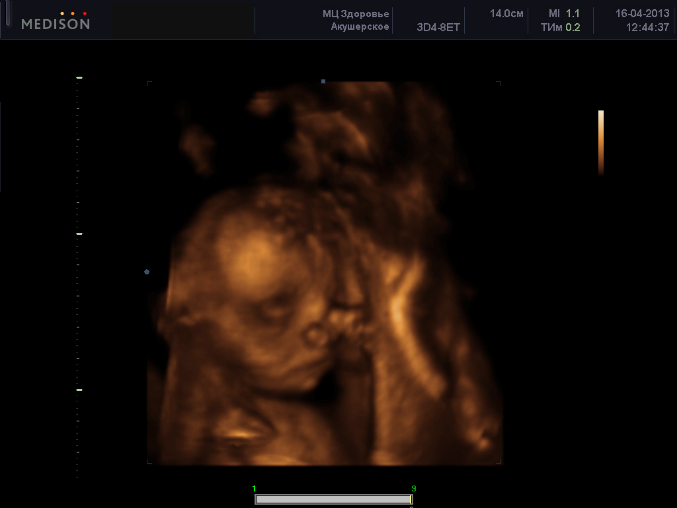

ВОТ наше первое узи в 3д )))Врач Шуана Алиева узи нам обошлось с записью на диск 3700) удовольствие не дешовое еще и огорчило что малышка прикрылась ручками((((моя любимая доча спала и не желала показывать личико((расти моя конфетка на радость мамочки и папочки))!!!!